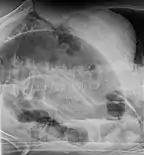

Coronal CT of the abdomen, demonstrating a volvulus as indicated by twisting of the bowel stock